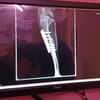

Gute-Laune-Hündin LILLY kam mit verkrümmten Hinterbeinen auf die Welt und wurde im Februar am linken Hinterbein operiert. Durch diese Operation konnte LILLY ein großer Teil an Lebensqualität gegeben werden, aber vollkommen gesund wird LILLY dadurch nicht. Durch eine geringe Gabe an Schmerzmitteln kann sie ein gutes und schönes Leben führen.